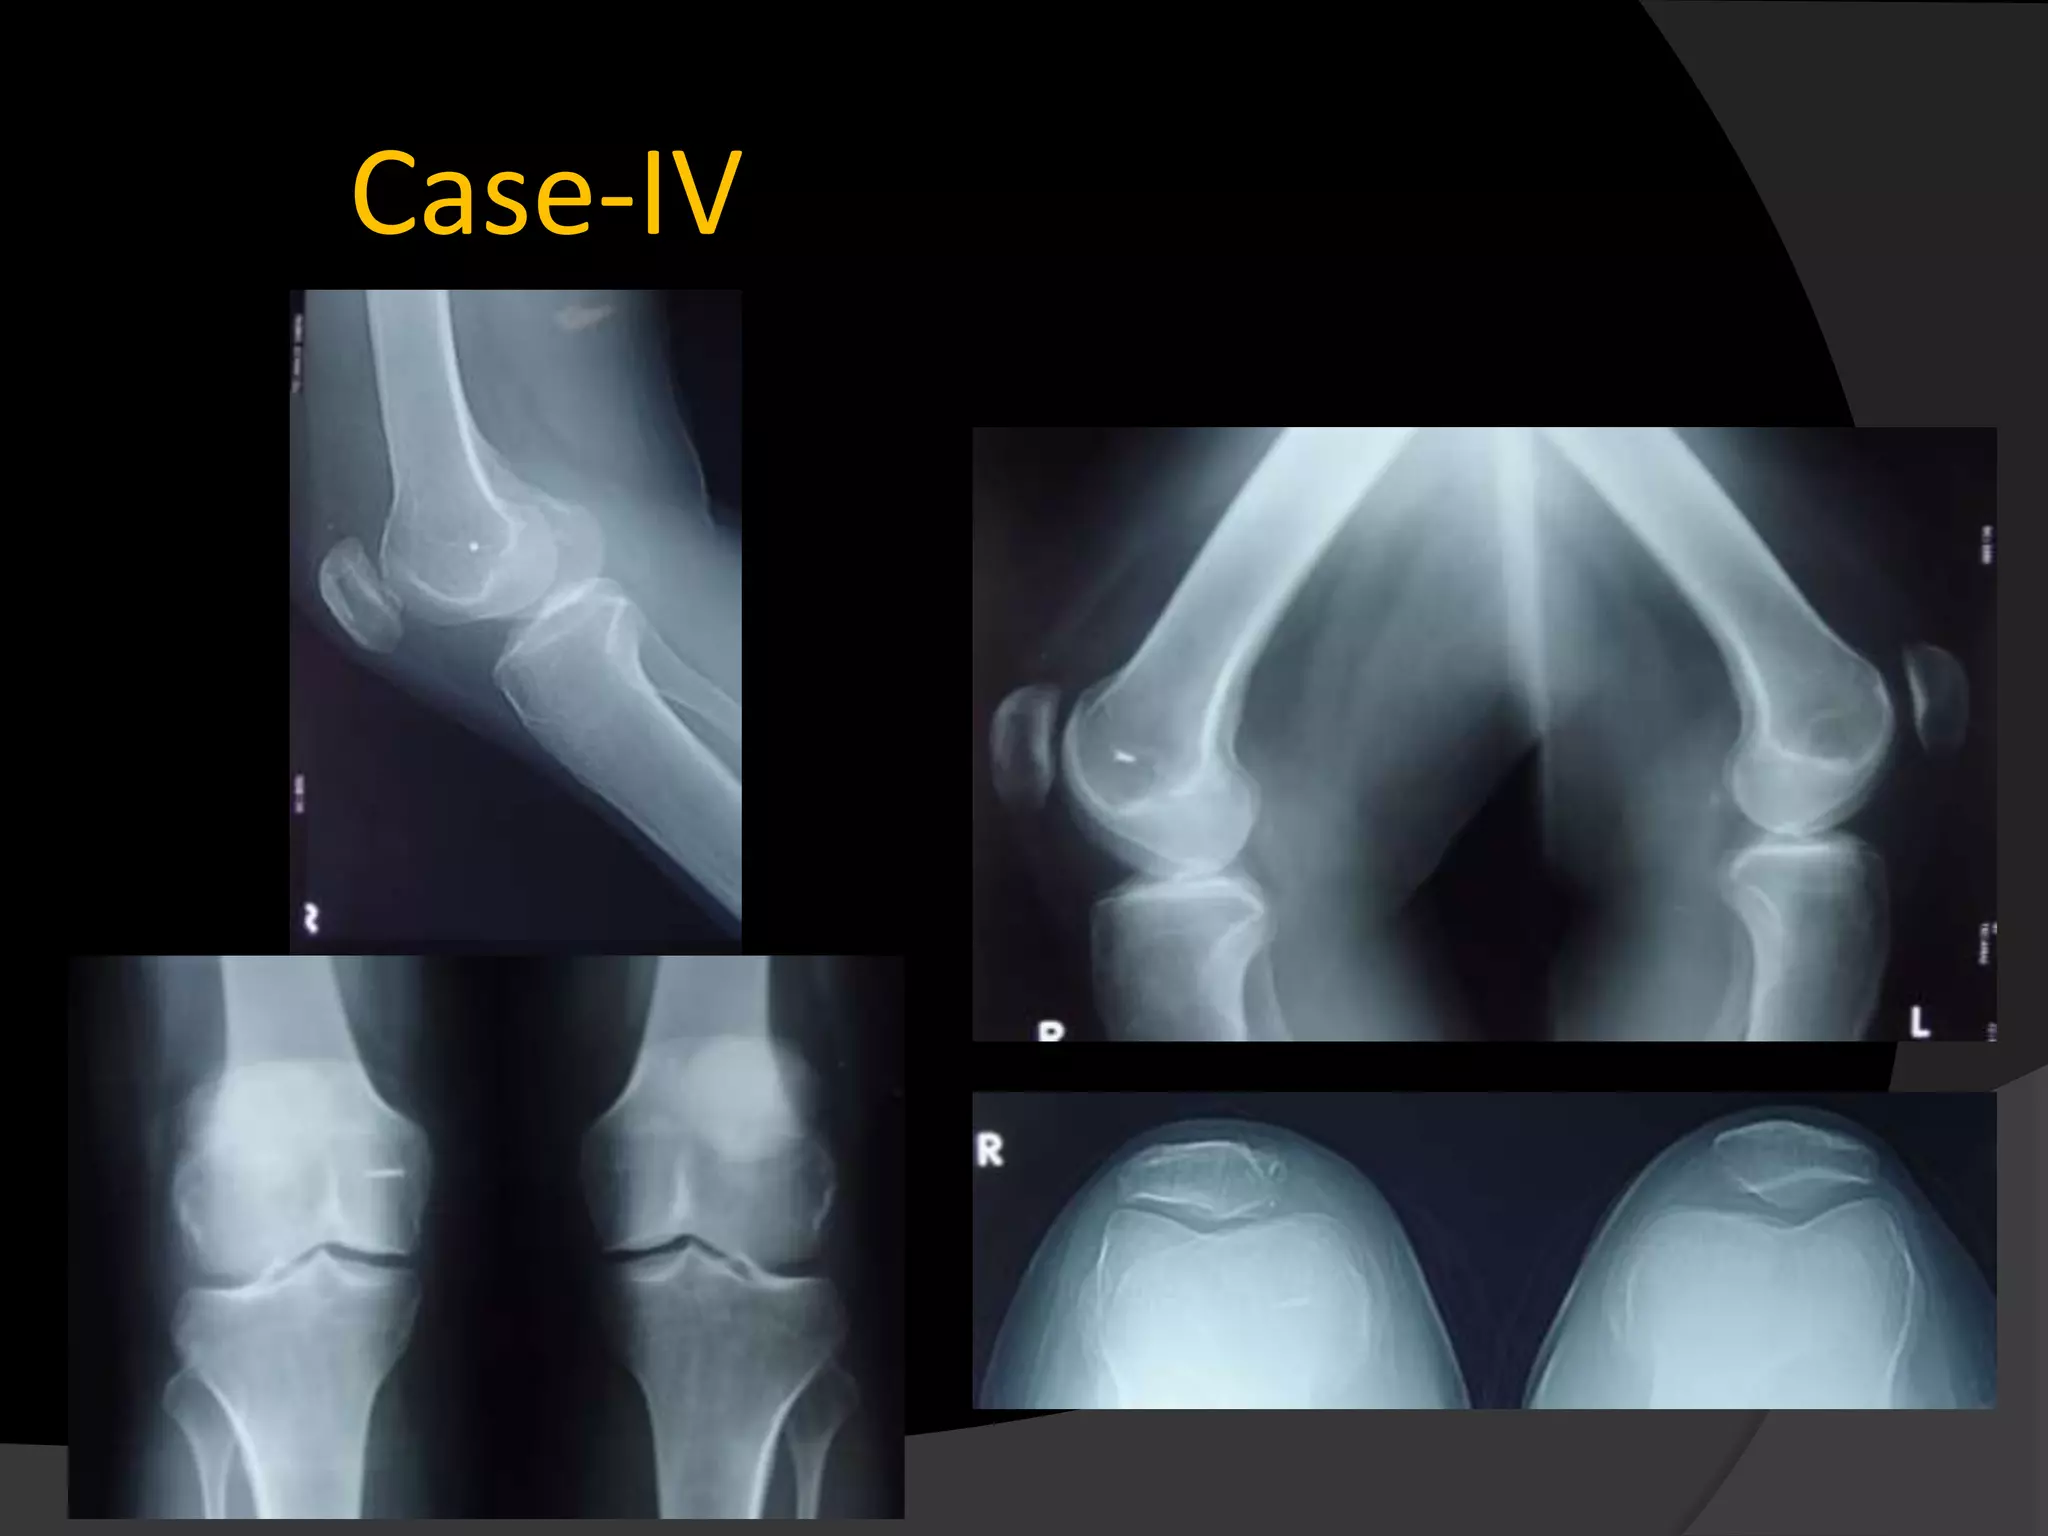

Case-IV

Material and methods 14 Patients with patellar instability were enrolled in this study from 2008-2012 5 habitual dislocation 9 Recurrent dislocation Medial patellofemoral ligament pathology was confirmed by both clinical and radiological examination. Apprension test was positive in 12 patients Average Q angle..